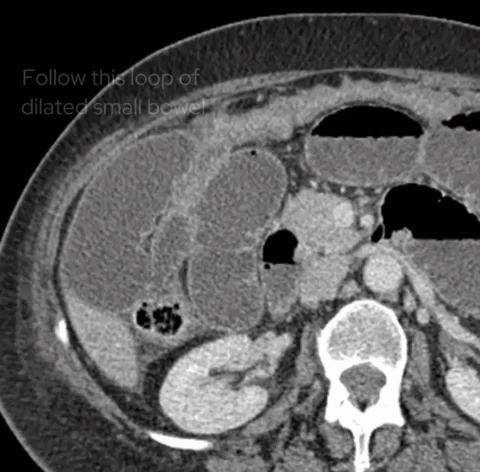

If we look at the psoas muscles on this scan below we can see there is some asymmetry . The right psoas is larger than the left and we’ve lost some of the fat planes within the muscle.

Compare the psoas muscles side by side. The right sided psoas muscle appears expanded with a loss of its normal fat planes.

Also as we scroll down we can see there is fat stranding surrounding the psoas muscle extending into the pelvis.

There is fat stranding surrounding the psoas extending into the pelvis.